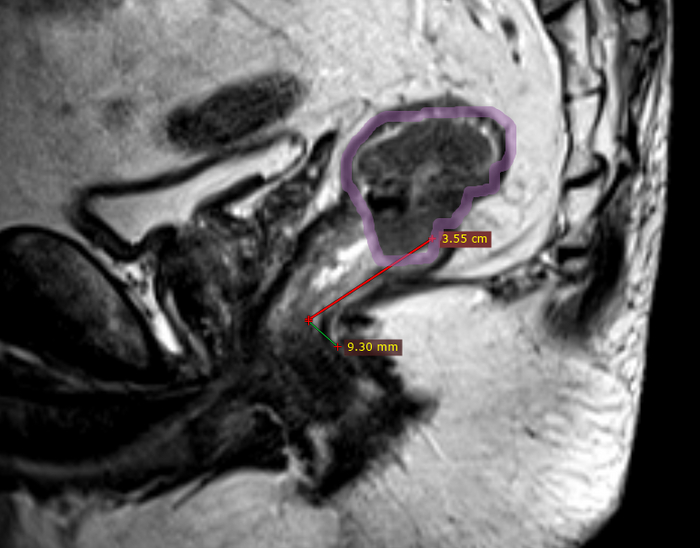

Ладно, обследуем. МРТ, КоТэ...

Крупная опухоль и пучок лимфоузлов. Но отдаленных метастазов нет.

Рак прямой кишки cT3N2M0 III стадия.

Суд онкоконсилиум присуждает химиолучевую терапию первым этапом. Пациент отправляется в соответствующее учреждение. Потом уже к нам, удалять остаток. С временной стомой, восстановлением...